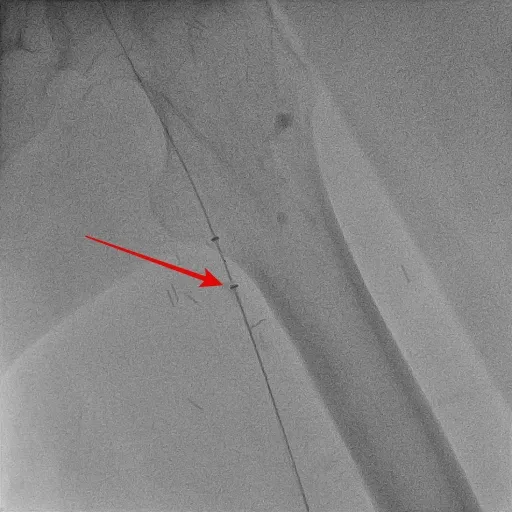

醫師利用機械性血栓抽吸導管移除血栓。亞大醫院提供

張育晟指出,為了增強治療效果、減少出血風險,治療時先將微導管由鼠蹊部靜脈伸入到栓塞處,再放置本身有許多側孔、專門溶栓的噴泉導管,將溶栓藥物以較低劑量的方式直接作用在血栓中,再以機械性血栓抽吸導管,快速將血栓移除,治療穩定後繼續針對黑色素瘤的部分作進一步的評估和治療。